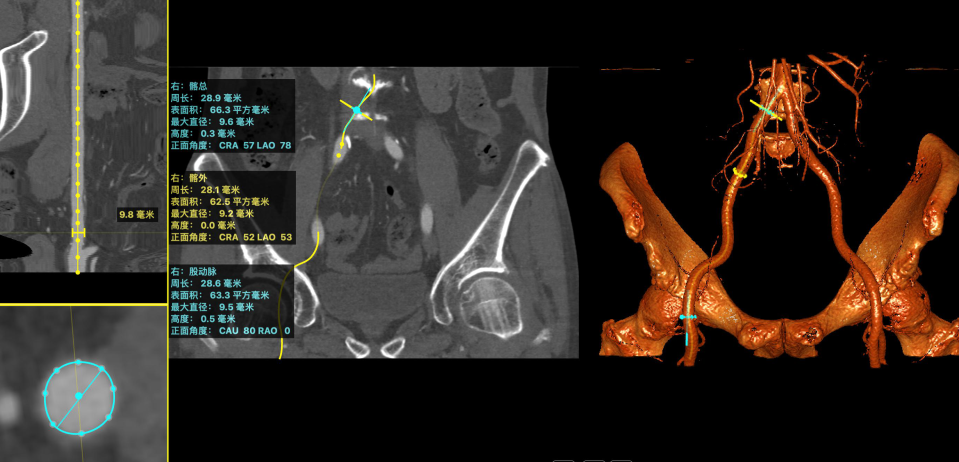

入路情况

横位心角度:70度

综合评估选择22mm球囊,TAV27瓣膜。如22mm球囊预扩张无明显腰征,且有明显瓣周反流,选用TAV27瓣膜。入路两侧股动脉轻度迂曲,左侧髂总均有钙化斑块。入路直径大于7mm,入路以右路为主,用22F大鞘。该患者年前超声报告提示EF值只有29,术前超声提示EF恢复到46,且升主和STJ增宽明显,考虑可能出现循环崩溃情况,提前做好相关预案。